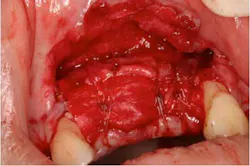

Fig. 11